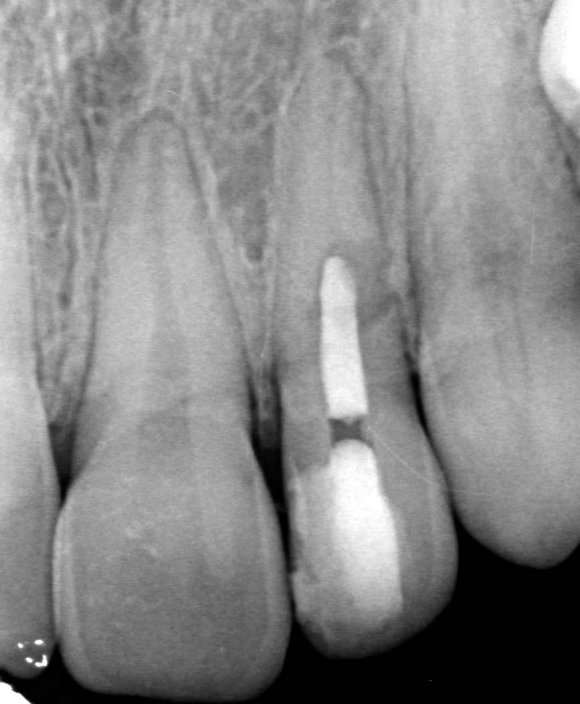

The X-ray snapshots showed signs of internal resorption in tooth 2.2.

The CBCT revealed intraroot perforating resorption on the vestibular root surface. In addition, a possible cause of resorption was identified as Oehlers' Type I invagination (1957), which was based on the radiological findings. According to the classification, Type I invagination is covered with enamel and is located within the coronal part, extending no further than the enamel-dentin junction. The authors believe that the infected invagination zone with subsequent creeping infection of the root pulp brought about the resorption. The response to the cold stimulus was very insignificant, especially in comparison with tooth 12. This made it clear that an irreversible destructive process is going on in the damaged tooth. Since the patient was planning orthodontic treatment and the resorption process could grow worse, it was decided to conduct endodontic treatment.